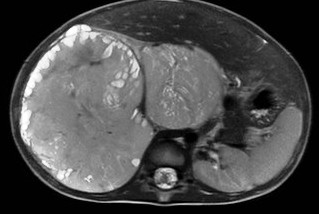

Wilms tumor. It is the most common kidney tumor in childhood that appears between 2-5 years of age. It is usually only noted when the tumor is palpable as an abdominal mass. Hematuria, hypertension, vomiting and abdominal pain are also part of the clinical picture. US examination is a basic method in both the diagnostics and the follow-up of the tumor. The tumor is normally seen as a homogenous or an inhomogeneous mass, dislocating the pyelon and the surrounding retroperitoneal blood vessels. It is important to rule out any lesion in the other kidney. MRI examination: gives a picture of the entire abdomen, kidneys included. Nodal metastases, tumor thrombus are well depictable. CT-examination: is to be chosen if MRI is not available. The tumor shows an inhomogeneous contrast enhancement and pulmonary metastases (invisible to x-ray examination) are also depictable.

Image

28. MRI examination axial, T2weighted sequence. A solid mass arising from the right kidney and filling out the right side of the abdomen, with peripheral follicular cystic components. Wilms tumor. (with the courtesy of Dr. Gábor Rudas)